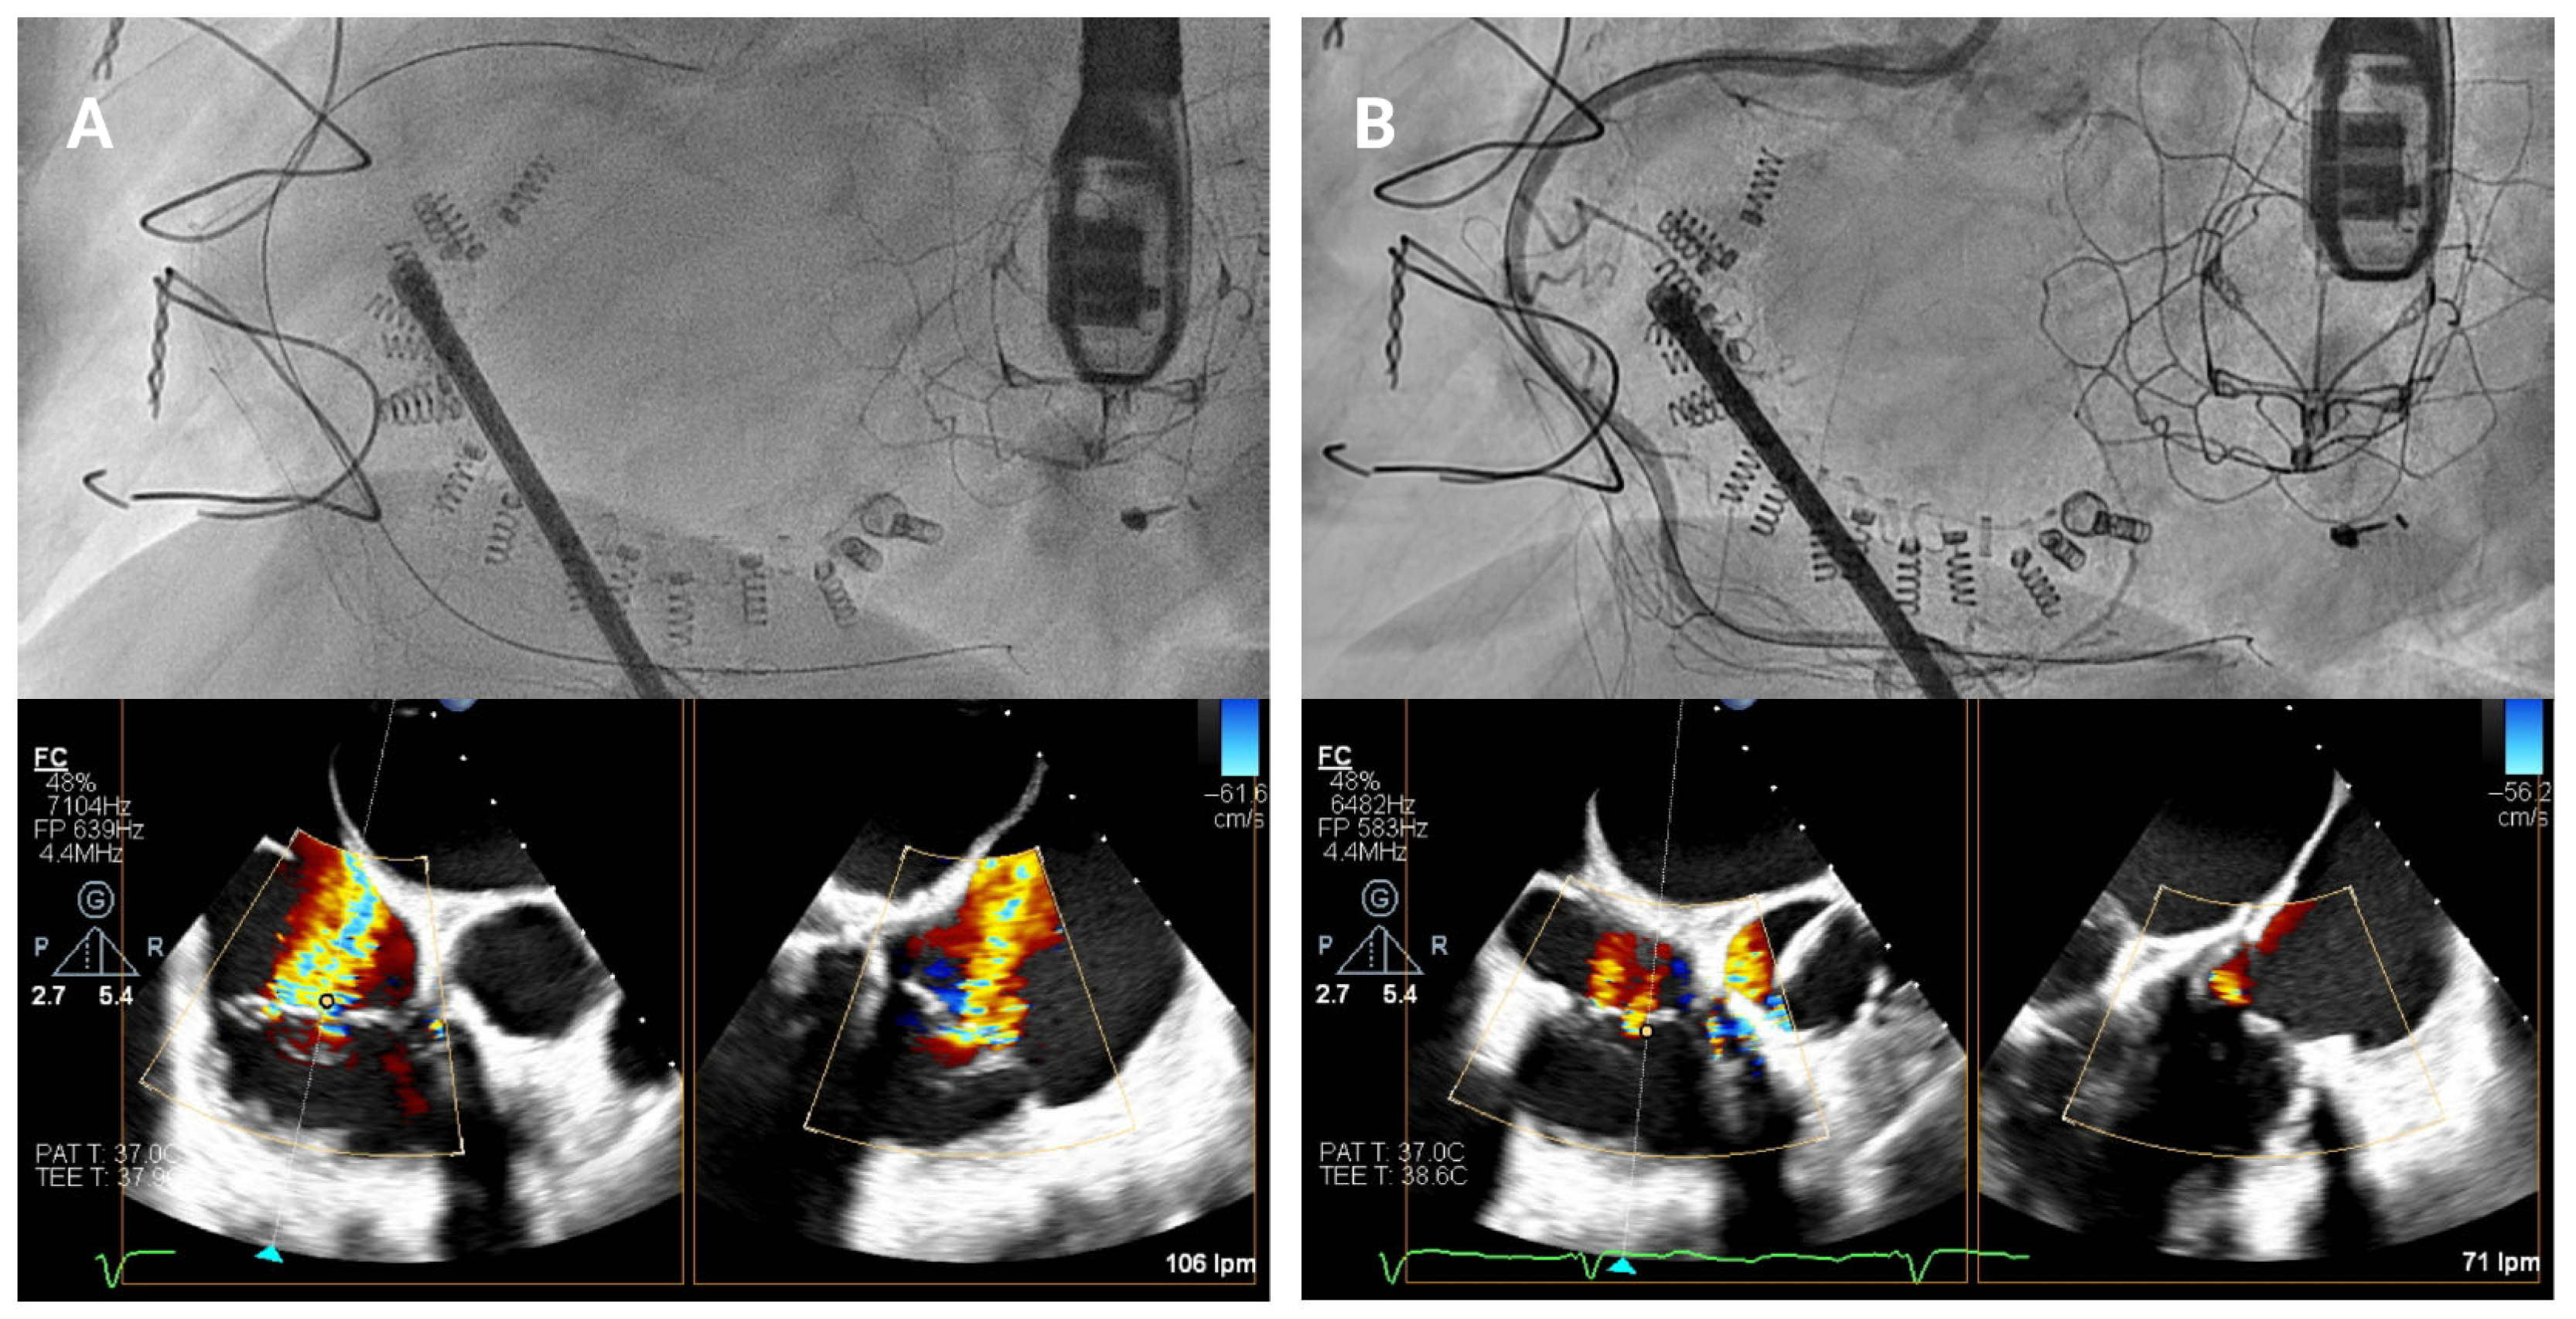

4.3.1. First Anchor Positioning (Anteroseptal Commissure)

The first anchor is positioned in the fibrous tissue anterior to the tricuspid annulus, close to the aorta, at least 25 mm from the center of aortic valve (

Figure 5A). The mid-esophageal right ventricular inflow-outflow view and transgastric right ventricular basal views are used to confirm the orientation of the IC [

10,

11]. It is essential that the IC tip is directed away from the aortic root to avoid complications. Fluoroscopy is performed using the LAO and RAO projections to verify directional accuracy, ensuring that the catheter does not misalign toward the aortic root or the RCA.

4.3.2. Anterior Annulus Anchoring

Once the first anchor is released, the procedure progresses toward the anterior annulus (

Figure 5B). TEE views, such as the transgastric views at 40–60° and mid-esophageal views at 50–70°, provide crucial information for visualizing the IC’s position along the anterior segment of the annulus [

11]. Biplane and multiplanar reconstruction techniques enhance visualization, allowing for more accurate device placement. Fluoroscopically, the RAO projection guides the implant catheter (IC) along the annulus and ensures correct anchor positioning relative to the valvular structures. Before release, a “push–pull” test is performed under combined echocardiographic and fluoroscopic (RAO) guidance. On echocardiography, pulling allows observation of the annulus being drawn toward the IC (

Supplemental Video S1). On fluoroscopy, pulling causes the anchor to move slightly from its original position, resulting in traction of the previously deployed band, anchors, and the RCA wire.

Figure 5.

Anterior tricuspid annulus anchoring. (A) First anchor placement in the fibrous tissue anterior to the tricuspid annulus, near the aorta. Orientation is confirmed using mid-esophageal right ventricular inflow-outflow and transgastric right ventricular basal views, along with fluoroscopy in an RAO projection. (B) Subsequent advancement of the implant catheter along the anterior annulus through transgastric and mid-esophageal views (40–70°) and multiplanar reconstruction.